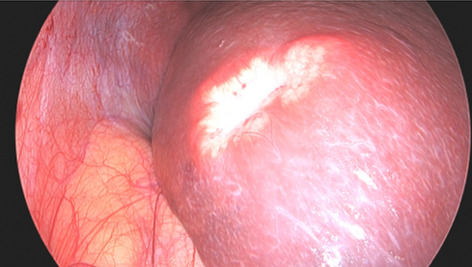

Background: Per-oral endoscopic myotomy (POEM) is an effective treatment for achalasia. Efficacy is equivalent to Laparoscopic Heller’s myotomy with the advantage of minimal access and shorter length of stay. Post-operative reflux rates are higher in POEM. The Functional Luminal Imaging Probe (FLIP) allows intraoperative measurement of lower oesophageal distensibility during per-oral endoscopic myotomy. In theory, this enables the operator to tailor the myotomy to ensure adequate distensibility whilst minimising post-operative reflux risk.

Methods: Two prospectively collected POEM databases were analysed from 2 UK tertiary upper GI centres.

The operators in each centre used intraoperative FLIP measurements to ensure adequate myotomy. Outcome measures included Eckardt score (where ≤ 3 indicated clinical success) and proton pump inhibitor use (PPI), collected at the first post-operative appointment. Length of stay was recorded, as were complications.

Results: 142 patients underwent POEM between 2015 and 2019 with 90% (128/142) clinical success. This improved to 93% (68/73) in the latter half of each series. 79% of the poor responders had previous interventions compared to 55% of responders (p = 0.09). Average post myotomy distensibility was 5.2 mm2/mmHg in responders and 3.11 in non-responders (p = 0.11). DI of > 4.5mm2/mmHg was associated with 100% clinical success. Myotomy length of < 7 cm was associated with 93% clinical success and 40% post op PPI use compared to 60% PPI use with longer myotomies. There were 2 type IIIa, 2 type IIIb and one type IV Clavien-Dindo complications.

Conclusion: This study represents one of the largest UK series of FLIP tailored per-oral endoscopic myotomy. FLIP allows intraoperative monitoring of oesophageal distensibility allowing tailoring of myotomies. Tailored myotomies ≤ 6 cm were effective and were associated with less PPI use post operatively. Early referral of patients to high volume centres, where myotomies can be tailored using FLIP may lead to improved outcomes. More collaborative data from high volume centres is needed to decipher optimal myotomy profiles.